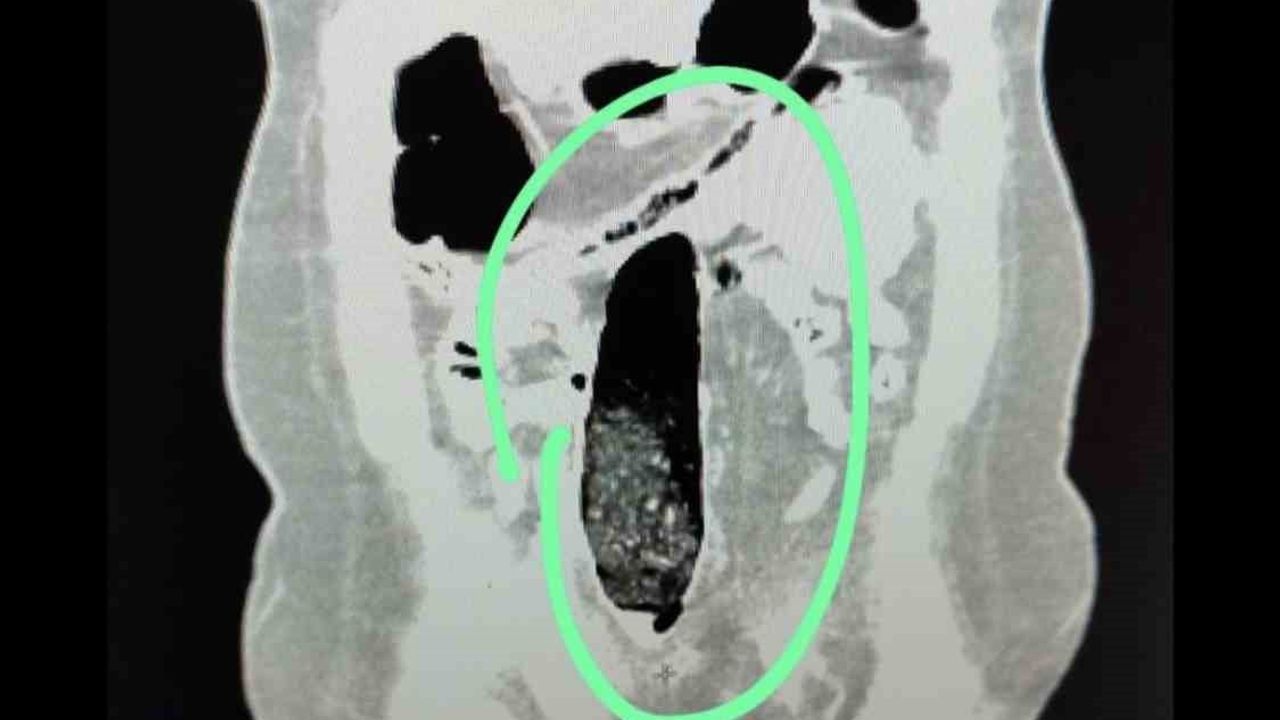

Durdurulan şehirler arası yolcu otobüsünde bulunan 2 İran uyruklu şahıs üzerinde yapılan kontrollerde şüpheli durum tespit edildi. Yapılan iç beden muayeneleri sonucunda şahısların vücutlarının doğal boşluklarında ve bağırsaklarında uyuşturucu madde bulunduğu belirlendi.

Tıbbi müdahale sonucu, F.V. isimli kadın şahıstan 3 parça halinde toplam 397,78 gram metamfetamin, S.İ. isimli erkek şahıstan ise 24 adet sentetik hap ile 3 parça halinde toplam 167,68 gram metamfetamin ele geçirildi.